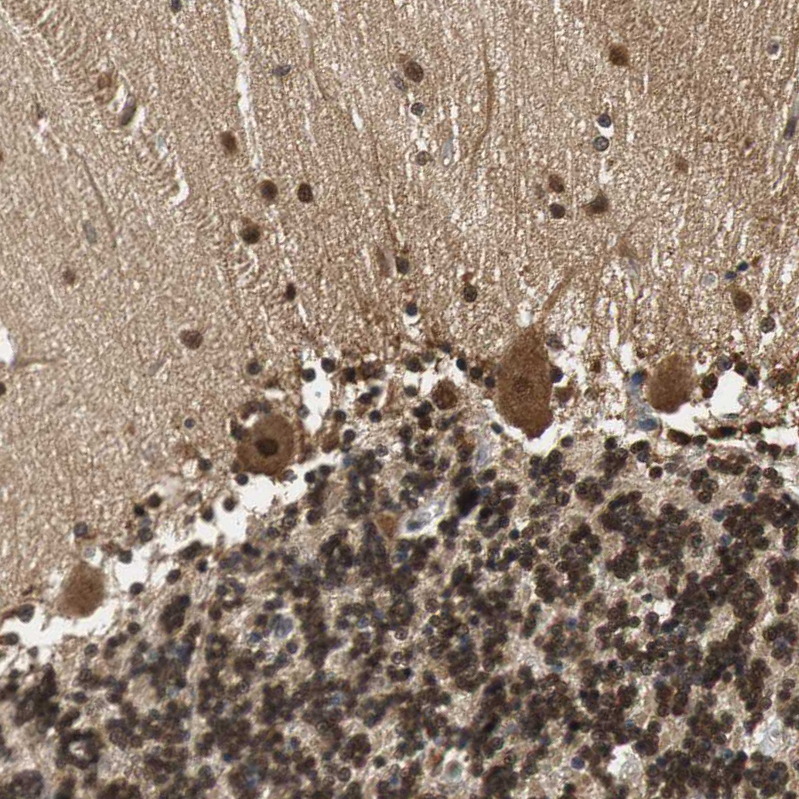

Immunohistochemical staining of human cerebral cortex shows moderate to strong cytoplasmic positivity in neurons and glial cells.